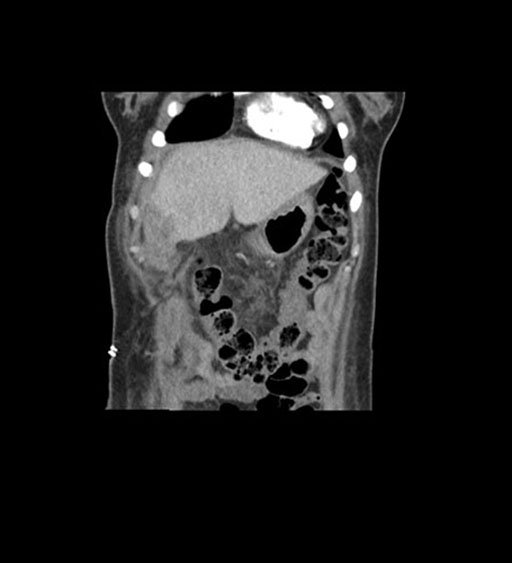

Imaging Analysis

Look through the patient's CT scan to identify any areas of concern for the necessary procedure.

Coronal Venous

Based on initial findings, which issue(s) would you be most concerned about?